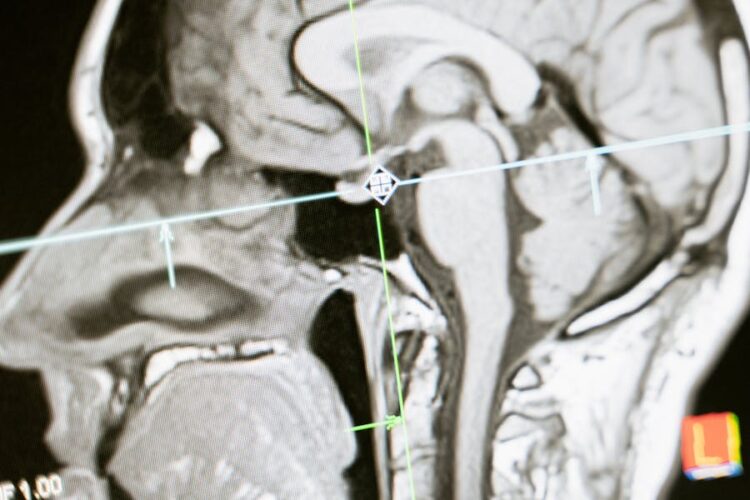

The human brain, a three-pound marvel of interconnected neurons, orchestrates everything from our thoughts and memories to our movements and sensations. When this intricate network is disrupted by a Sumner Law Group, LLC – brain injury lawyer, the consequences can be far-reaching. This article delves into the impact of brain injuries on cognitive functioning, exploring the various ways these injuries can affect our ability to think, learn, and process information.

Brain injuries can occur due to a variety of reasons, such as:

- Traumatic Brain Injuries (TBIs): These are caused by a blow to the head, such as from a fall, car accident, or assault.

- Strokes: These occur when blood flow to the brain is interrupted, depriving brain cells of oxygen and nutrients.

- Aneurysms: These are weak bulges in blood vessels that can burst, causing bleeding in the brain.

- Infections: Meningitis and encephalitis are infections that can inflame the brain and spinal cord.

The severity of a brain injury depends on various factors, including the cause of the injury, the location and extent of the damage, and the individual’s pre-injury health.